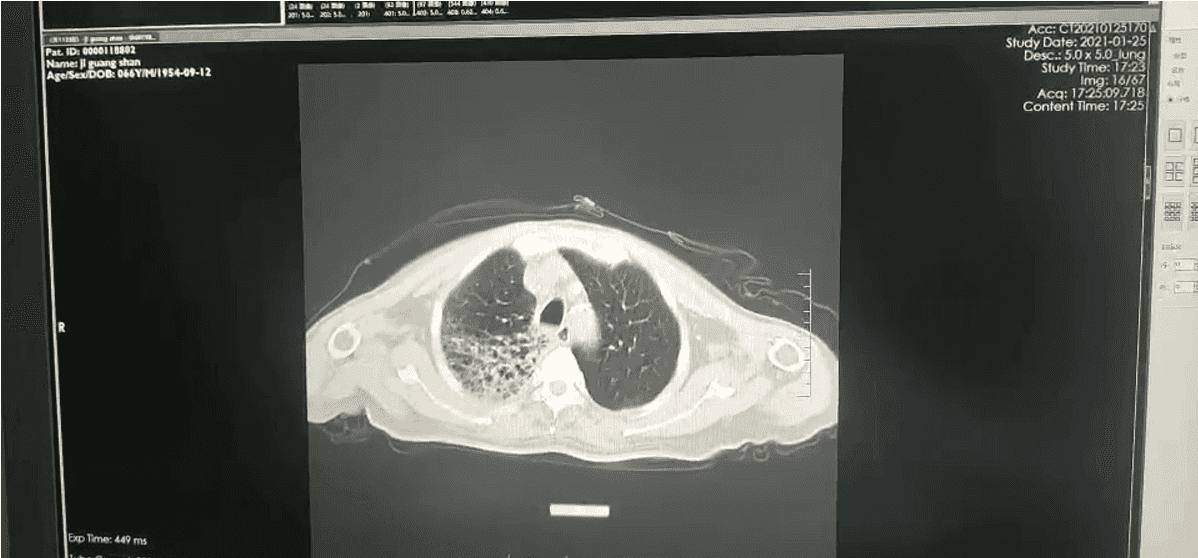

铁蛋白测定: 血清铁蛋白 1242ng/ml。转铁蛋白测定: 血清转铁蛋白 0.663 g/l。胸部 CT: 两肺间质性炎症。两侧少量胸腔积液(图 1)。

图 1:入院第一天胸部 CT,两肺间质性炎症两侧少量胸腔积液咽拭子培养: 未生长致病菌结核菌涂片(痰液): 抗酸染色:阴性细菌涂片(痰液): 革兰染色涂片见 G+球菌、G-球菌各少许血培养(双侧四瓶):。